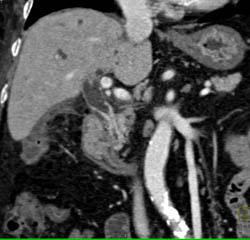

Cholangiocarcinoma of the Distal Common Bile Duct (CBD) Which Is Enhancing- See Full Sequence